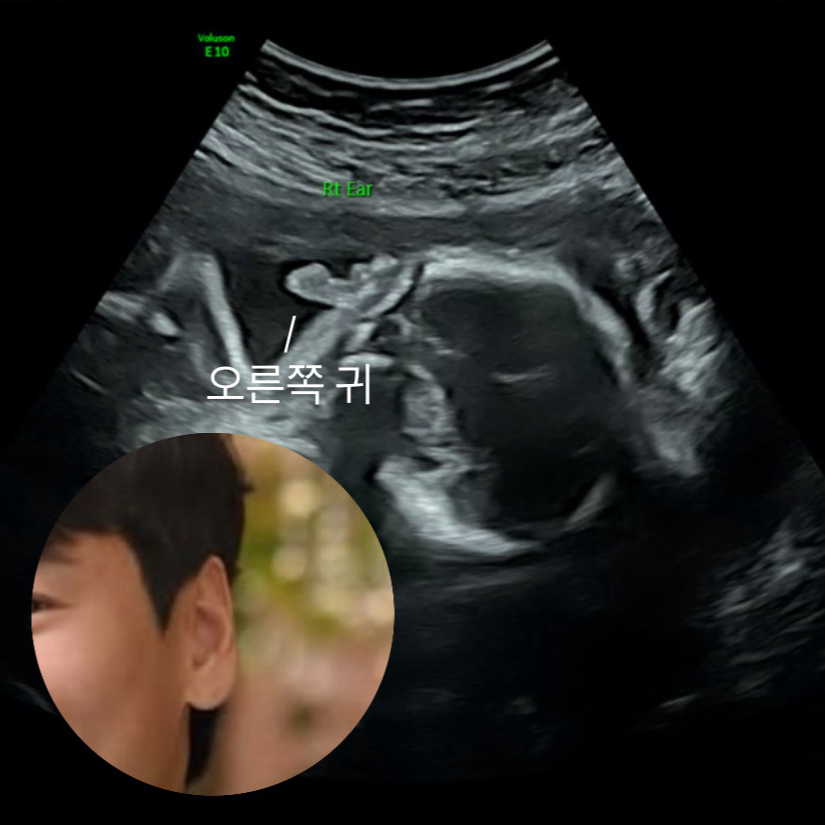

2차 정밀초음파 했던 날! 초음파 사진 어마어마하게 많이 받아서 넘 당황.. 초음파 앨범에 어떻게 기록해야 할지 대략난감.. 우리 완주 귀는 아빠 닮았구나..